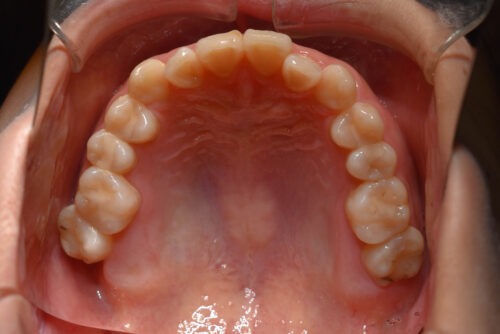

ワイヤー8か月後です。

矯正専門の 精密検査を行い

非抜歯矯正治療計画で

下顎は

ご自身の歯で かめるように

歯の欠損部は

全てスペースを閉じる

非抜歯矯正治療を開始しました。

本症例のように

歯科矯正用アンカースクリュー(デュアル・トップオートスクリュー)を利用し

下顎の後方移動を行うことで

歯を抜かない非抜歯矯正治療でも

受け口を整えることができます。